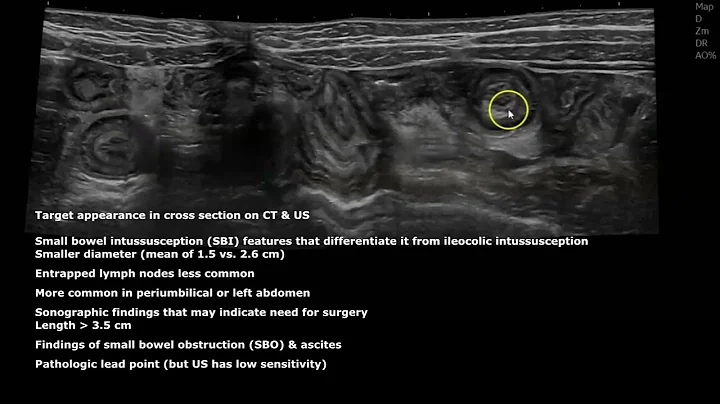

Invagination ! In Ultrasound

suitable for all #residents an medical doctor even how loves knowledge :) have a question?? comment please and ...